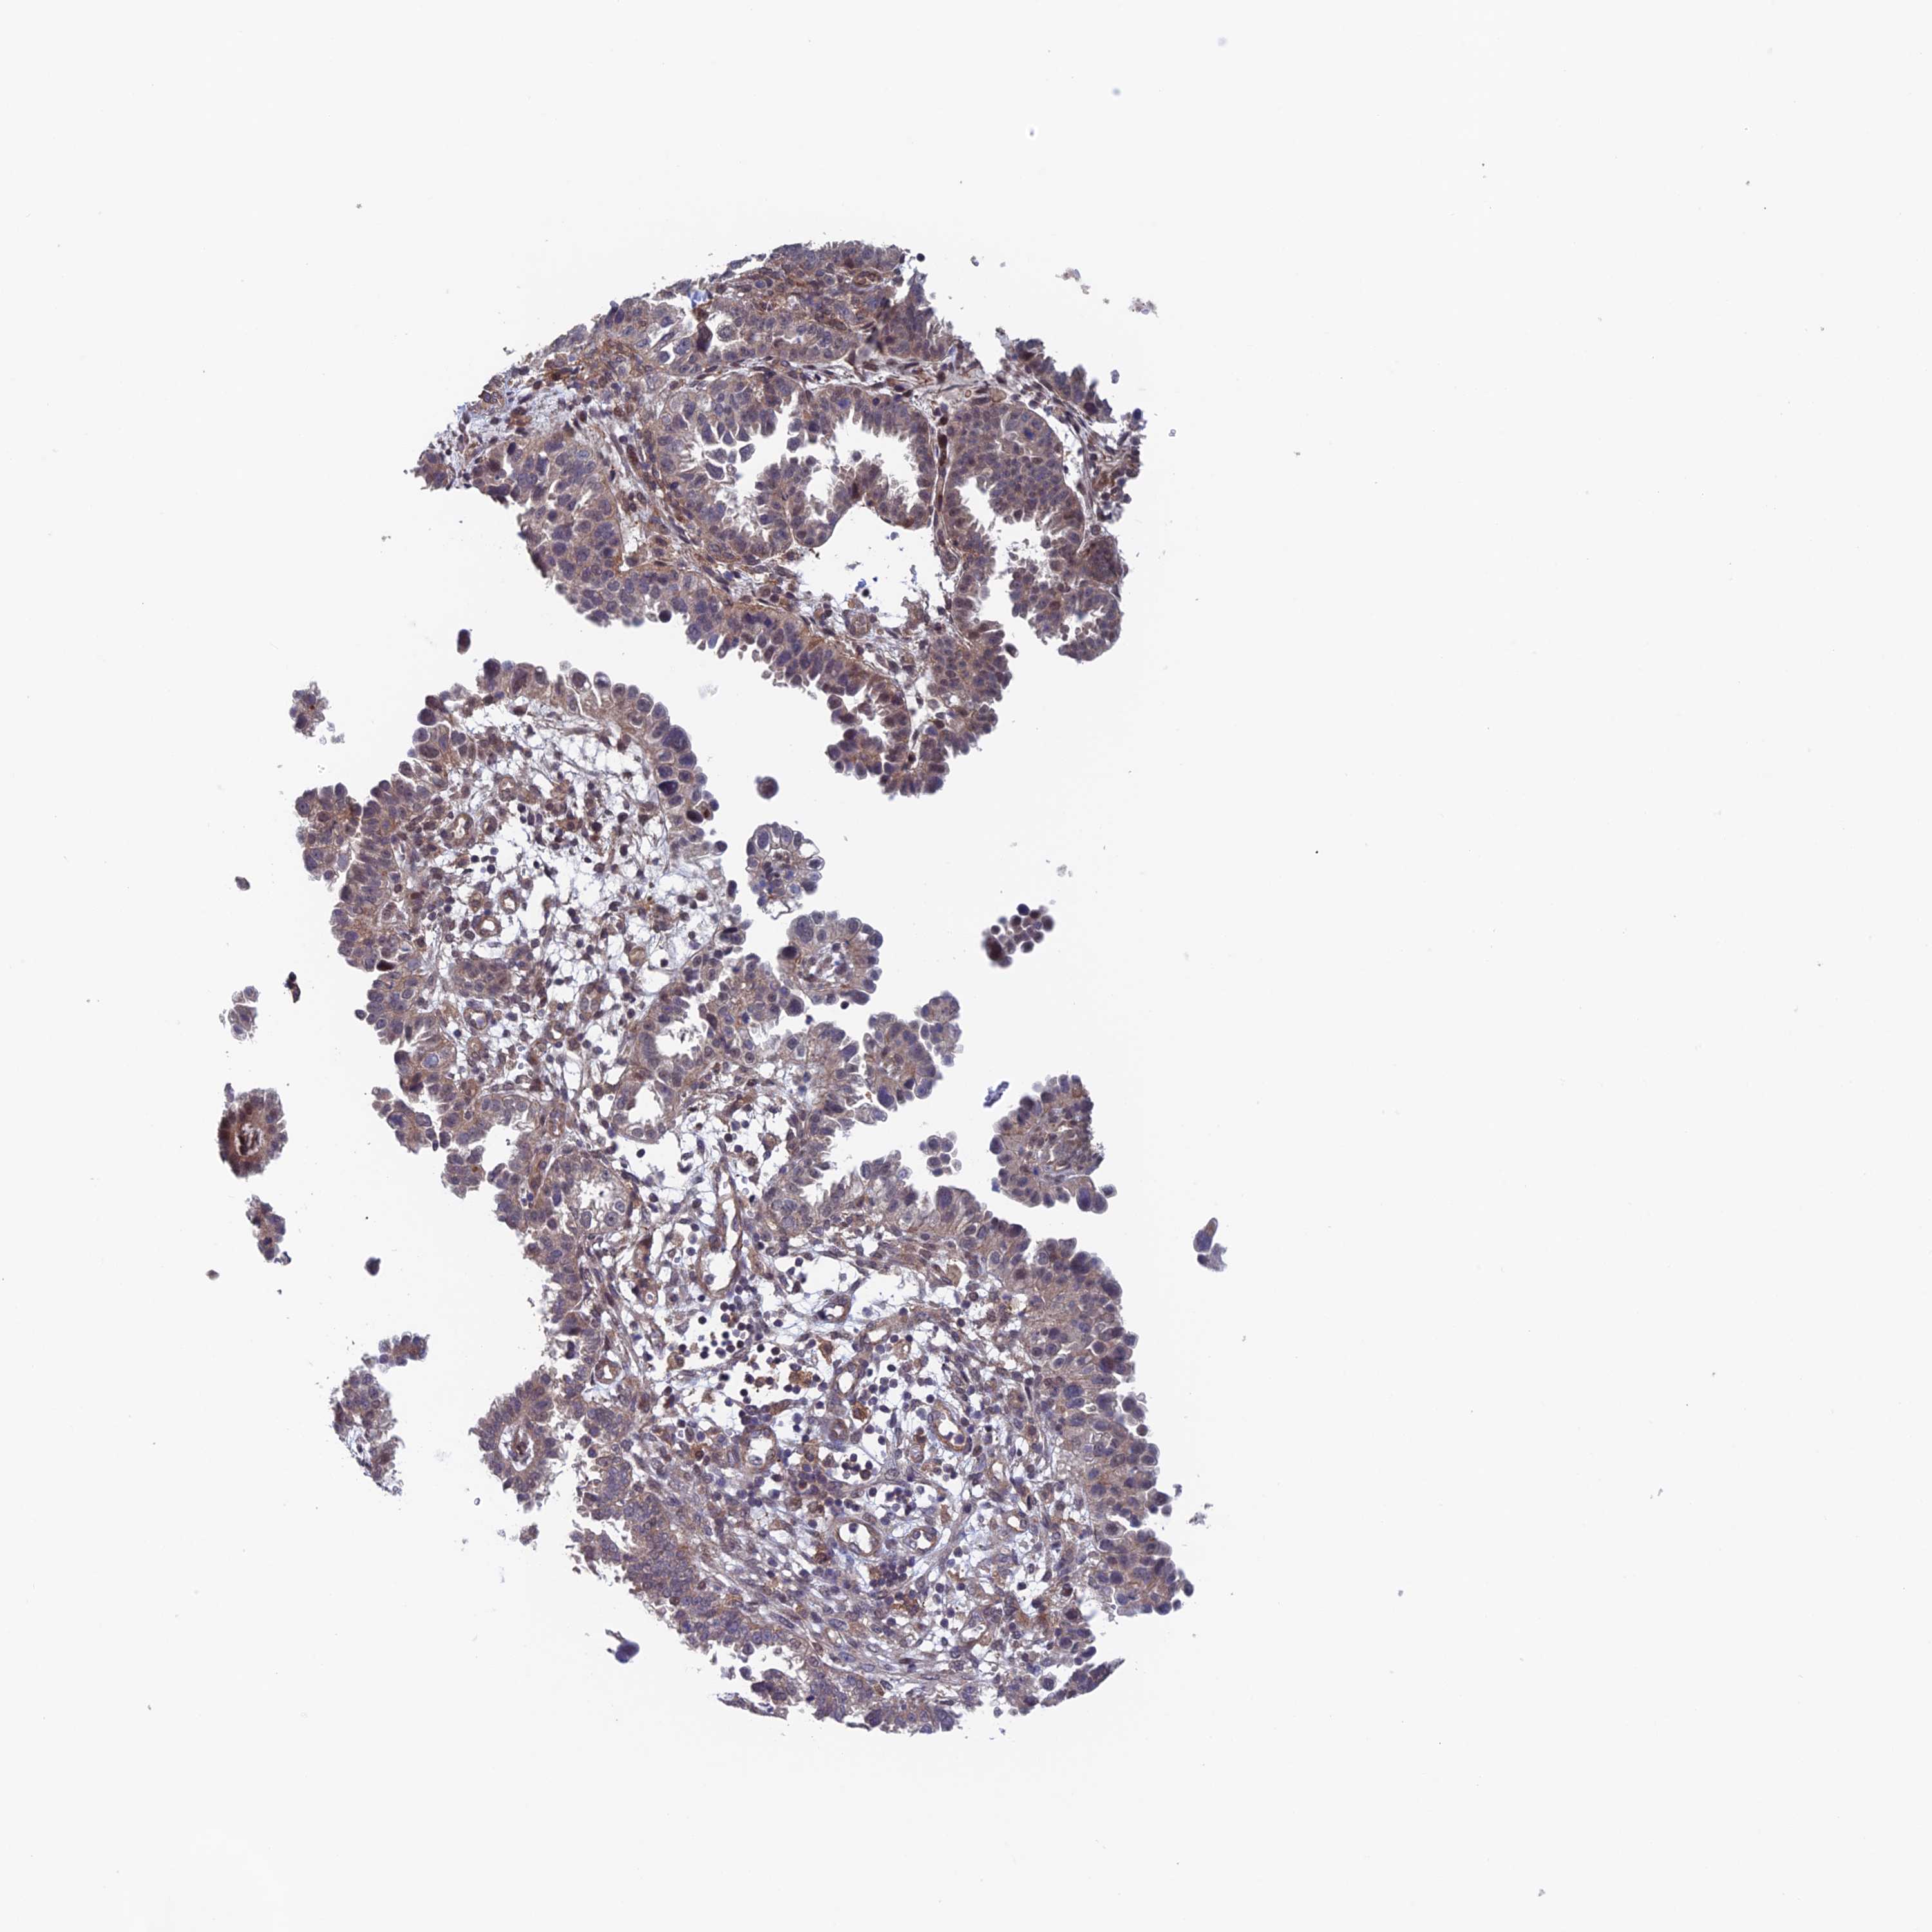

ENDOMETRIAL CANCER - Protein expressioni

A mouse-over function shows sample information and annotation data. Click on an image to view it in a full screen mode. Samples can be filtered based on level of antibody staining by selecting one or several of the following categories: high, medium, low and not detected. The assay and annotation is described here.

Note that samples used for immunohistochemistry by the Human Protein Atlas do not correspond to samples in the TCGA dataset.

Antibody stainingi

Antibody staining in the annotated cell types in the current human tissue is reported as not detected, low, medium, or high, based on conventional immunohistochemistry profiling in selected tissues. This score is based on the combination of the staining intensity and fraction of stained cells.

Each image is clickable and will lead to virtual microscopy that enables deeper exploration of all samples and also displays staining intensity scores, fraction scores and subcellular localization as well as patient and tissue information for each sample.

Antibody HPA044186

Antibody HPA063605

Staining

High

Medium

Low

Not detected

Intensity

Strong

Moderate

Weak

Negative

Quantity

>75%

75%-25%

<25%

None

Location

Nuclear

Cytoplasmic/membranous

Cytoplasmic/membranous,nuclear

Adenocarcinoma, metastatic, NOS